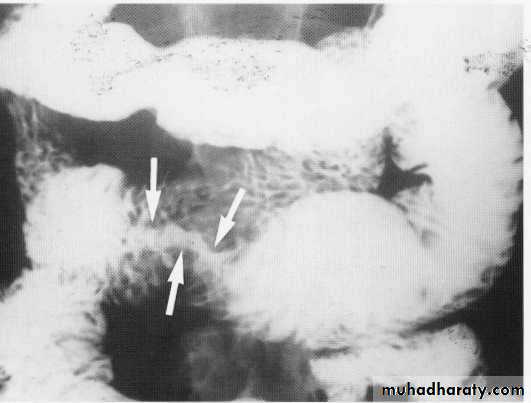

Chrons disease

Chrons stricture

Stricture + pericolic abscess